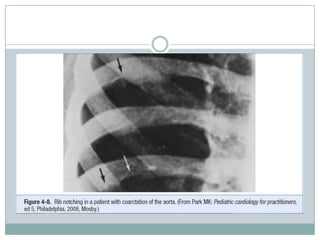

-Coarctation of the aorta

*Simultaneous palpation of the radial and femoral pulses is important to

determine if there is a delay in pulse transmission. In normal adults, the

upstrokes of the radial and femoral pulses normally appear simultaneously. A

delay in the onset of the femoral pulse, generally associated with a diminished

amplitude, suggests coarctation of the aorta.